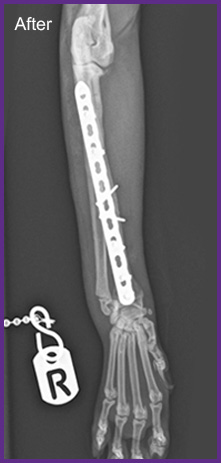

We offer general medical and surgical services with advanced diagnostic facilities. Also, we are one of the few clinics in Hong Kong that provide both CT Scan and MRI services for animals. Our team are equipped to provide detail nursing care for hospitalize pets.